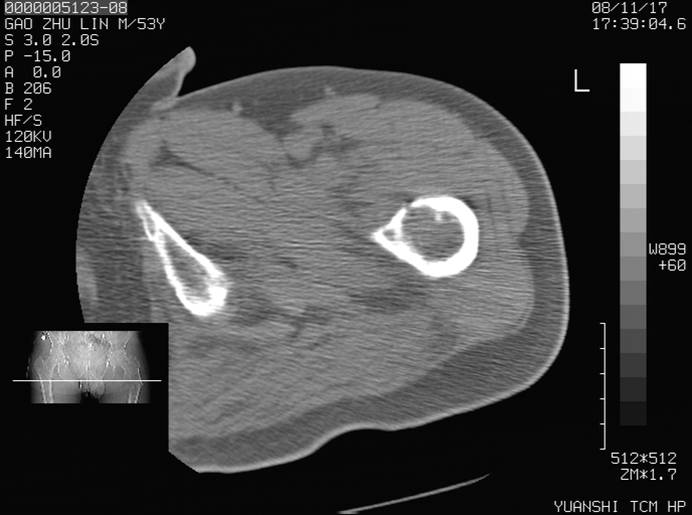

标题: CT16696:M53Y,左股骨上段骨折。 [打印本页]

标题: CT16696:M53Y,左股骨上段骨折。

左股骨上段外伤1个小时,左股骨上段疼痛。村医以腰椎间盘病变给以按摩及理疗数天。

图像不太清楚,左股骨上段外伤性骨折?病理性骨折?

左股骨上段粉碎性骨折

左股骨上段粉碎性骨折;建议上传骨窗看看是不是病理性的啊!

左股骨上段粉碎性骨折,不排除病理性骨折可能。

考虑骨肉瘤伴病理骨折

考虑:骨肉瘤伴病理骨折.

病理性骨折,考虑转移所致.